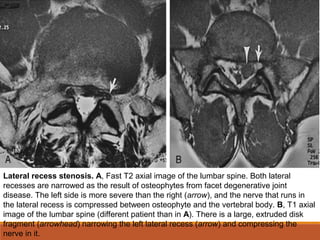

Lateral recess stenosis. A, Fast T2 axial image of the lumbar spine. Both lateral

recesses are narrowed as the result of osteophytes from facet degenerative joint

disease. The left side is more severe than the right (arrow), and the nerve that runs in

the lateral recess is compressed between osteophyte and the vertebral body. B, T1 axial

image of the lumbar spine (different patient than in A). There is a large, extruded disk

fragment (arrowhead) narrowing the left lateral recess (arrow) and compressing the

nerve in it.